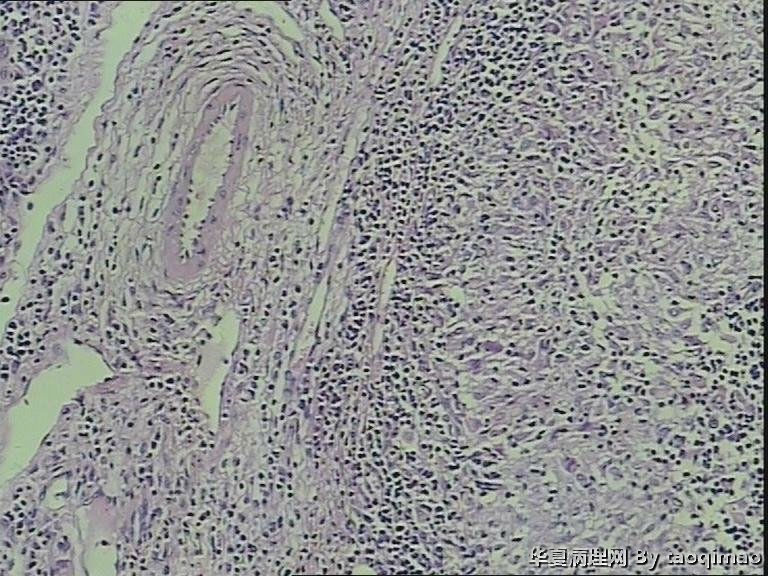

颈部淋巴结

• 颈部淋巴结图2

图2

刘秀敏女55岁,发现左颈肿物一年,质韧活动度差,无压痛。

粉红色球形肿物,1.7x1.5x0.7cm,包膜完整切面灰黄,质韧。

肉芽肿性炎  抗酸染色

淋巴结肉芽肿性病变,考虑结核的可能性大,做抗酸染色/PCR/联系临床

肉芽肿性炎,考虑结核

肉芽肿性炎,考虑结核。做个抗酸看看。

结核与结节病间鉴别

淋巴结结核